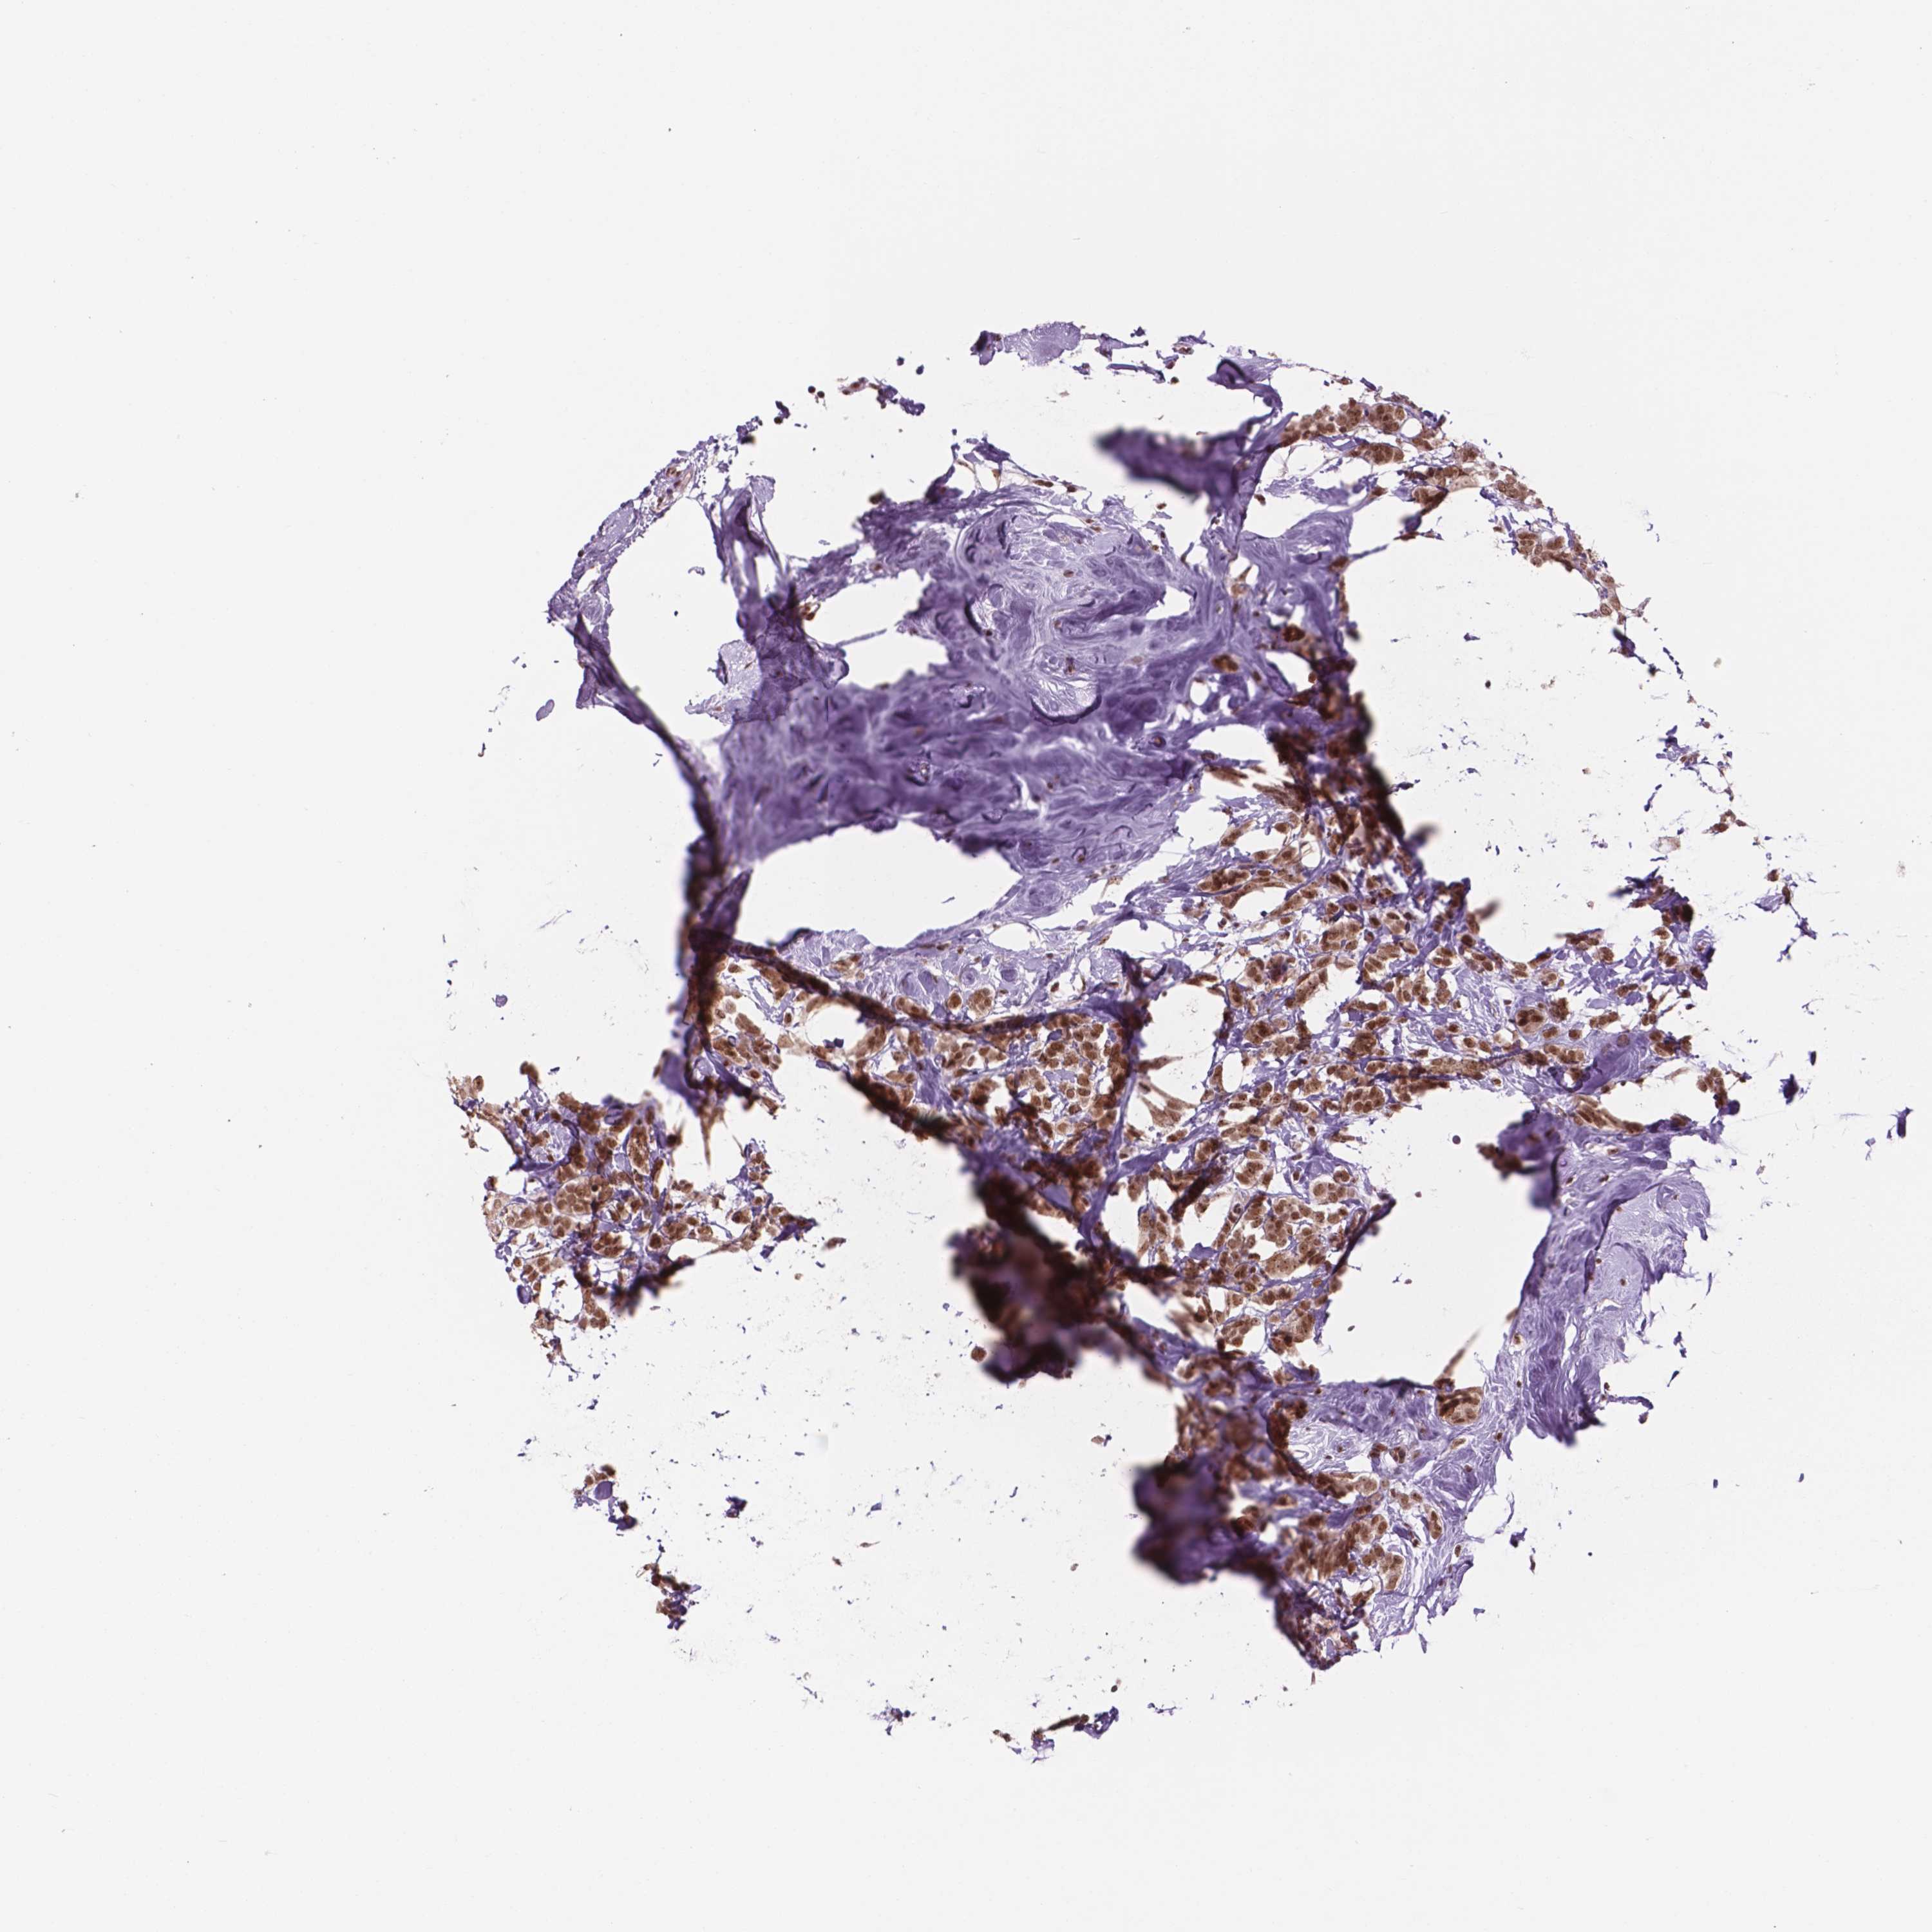

CANCER BREAST CANCER Show tissue menu

BRCA TCGA BRCA VALIDATION PROTEIN EXPRESSION

Breast cancer

Human cancer

Breast invasive carcinoma